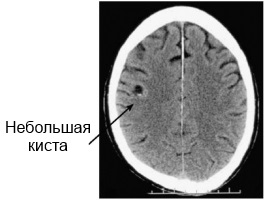

Щоб зрозуміти, що таке псевдокиста, уявіть порожнину, заповнену ліквором або іншою рідиною, оточену тоненьким чіткої оболонкою.

Провідним способом обстеження при псевдокисте вважається ультразвук. Однак він не дозволяє уважно оглянути стінки і внутрішній простір порожнини. Орієнтуються на конкретні ділянки, де зазвичай формується псевдокиста головного мозку у новонароджених.

Увагу звертають на великі півкулі мозку, бічні шлуночки, зону розташування голівки хвостатого ядра зорового бугра. Особливості локалізації дають можливість розрізнити псевдокисту, не сплутати її з істинною кістою.